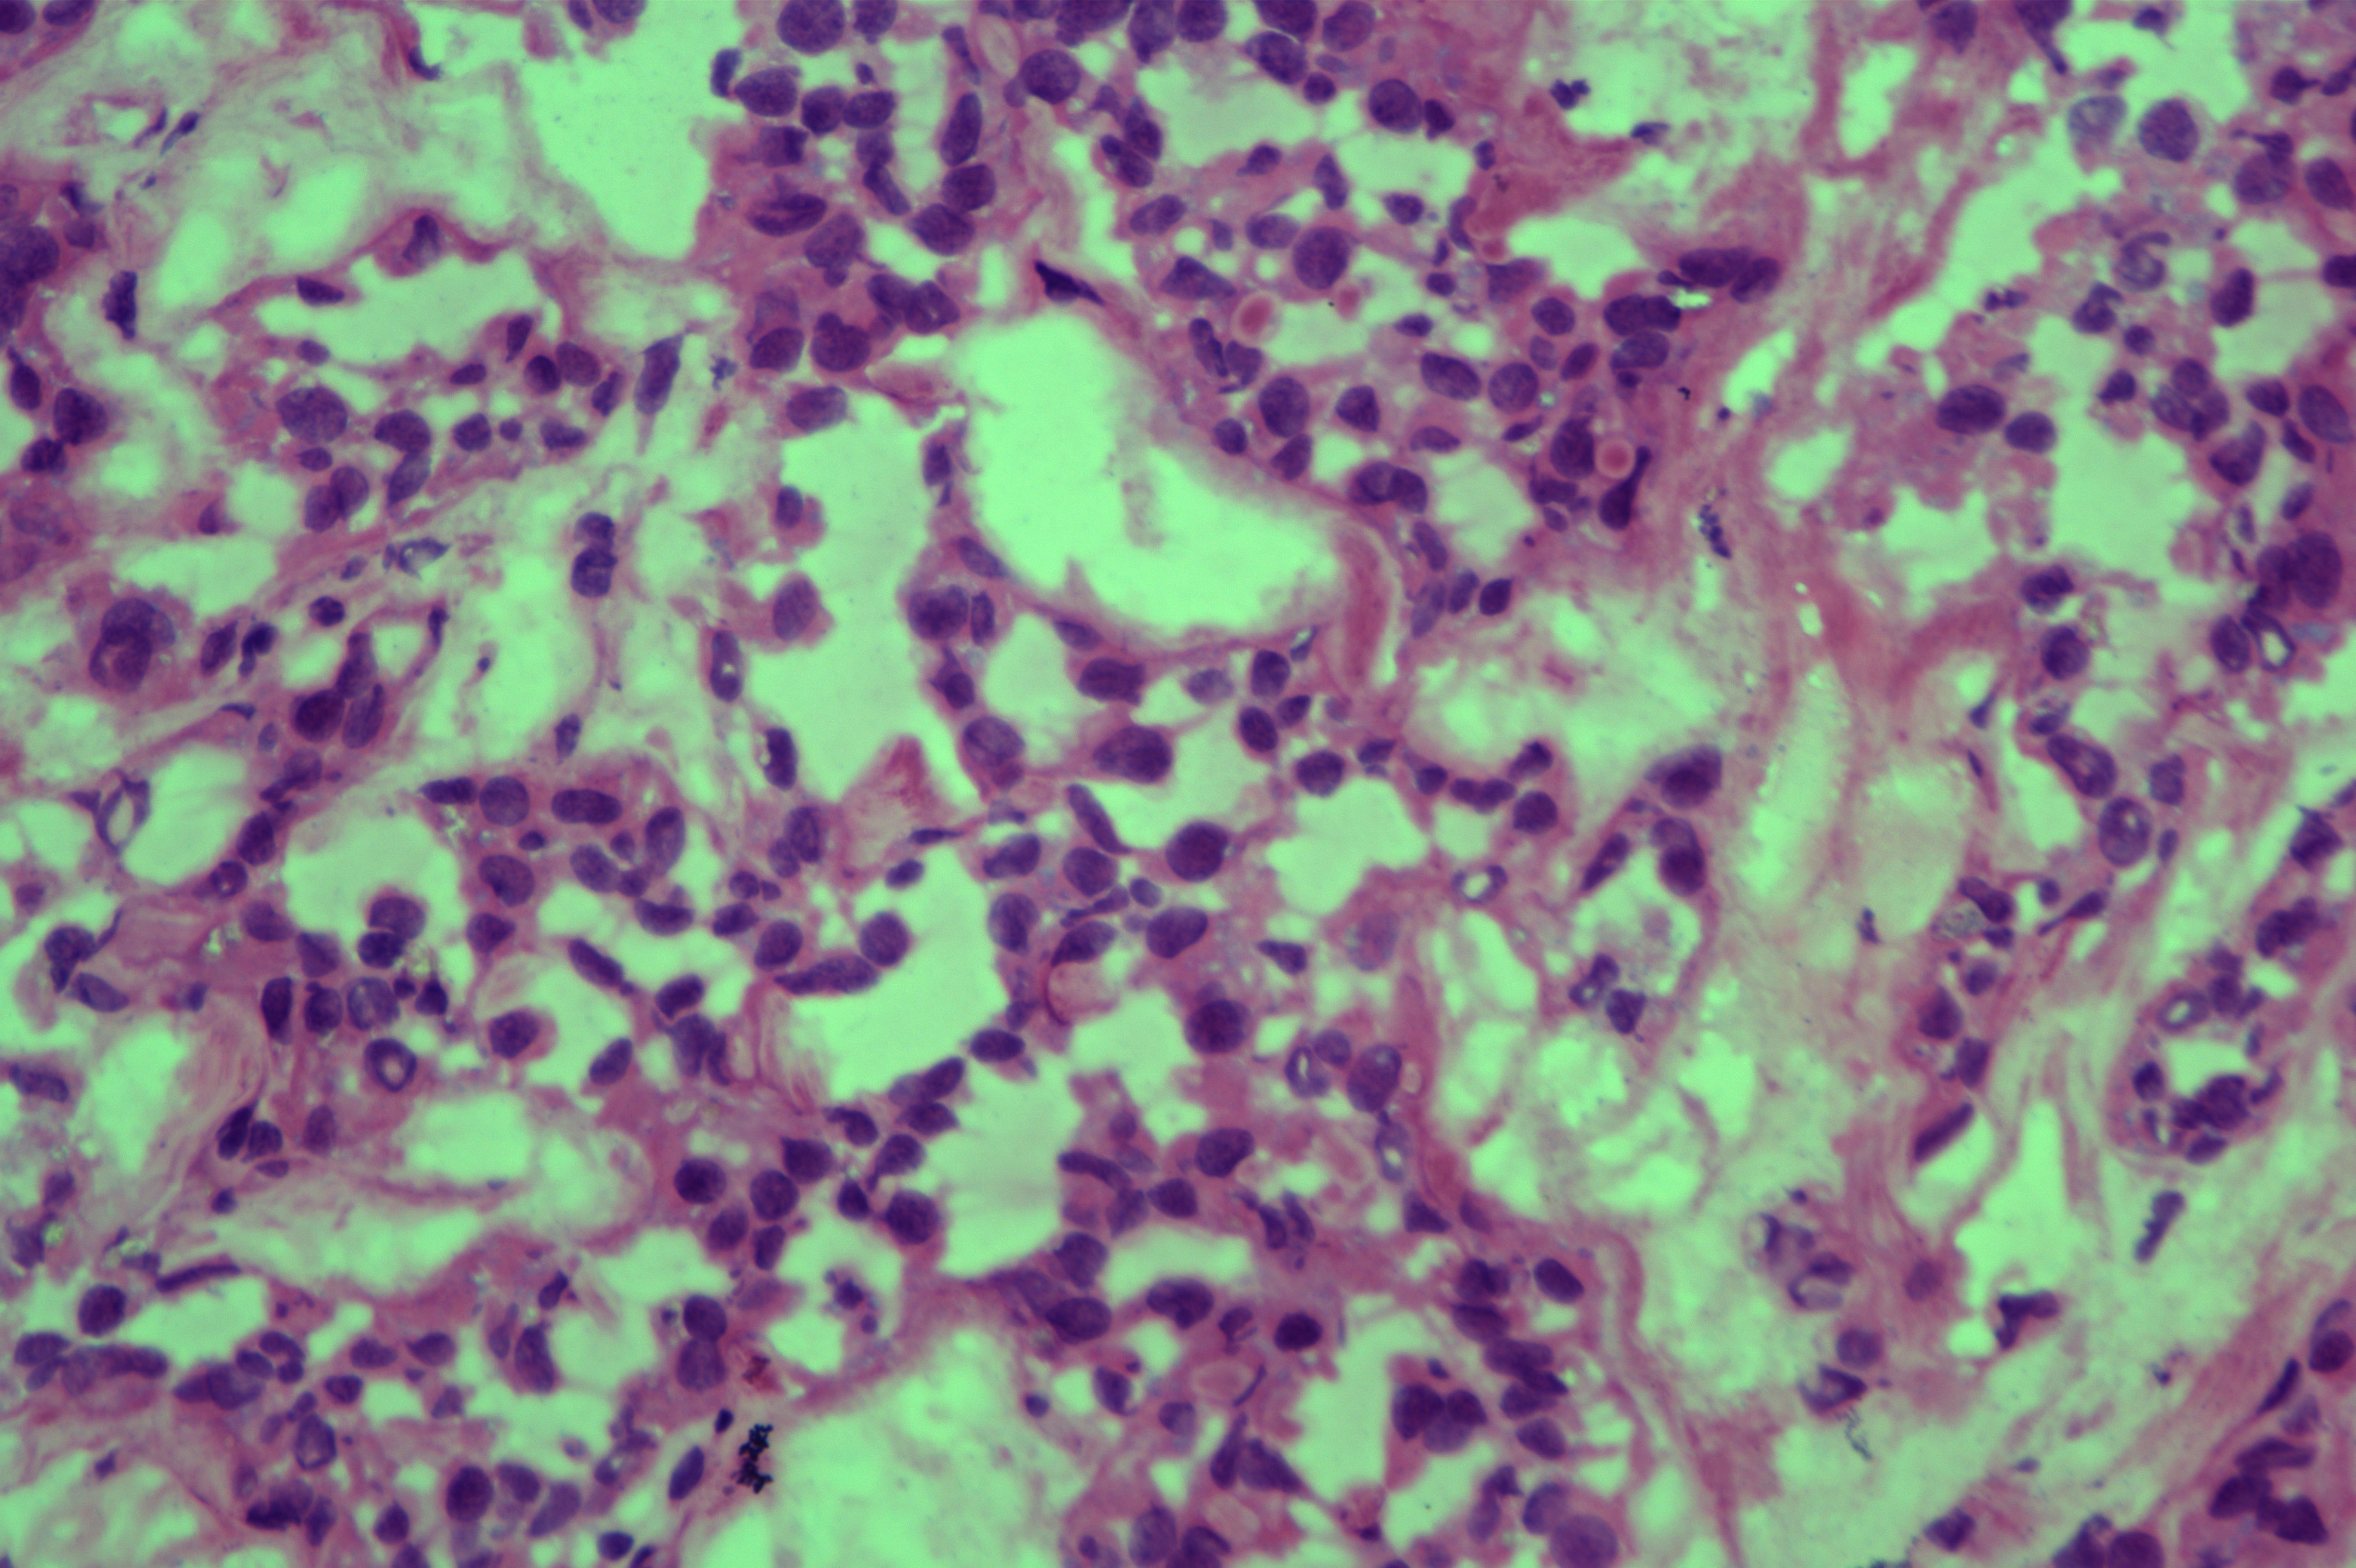

胰头肿物性质待诊

胰头肿物

上腹痛5天入院,核磁发现胰头囊肿,考虑良性

胰头囊肿

7x7x1.5cm囊肿一个,囊内见暗红色粘稠样物,囊壁厚0.7cm。

考虑为胰腺实性假乳头状瘤

会诊结果 :实性假乳头状瘤